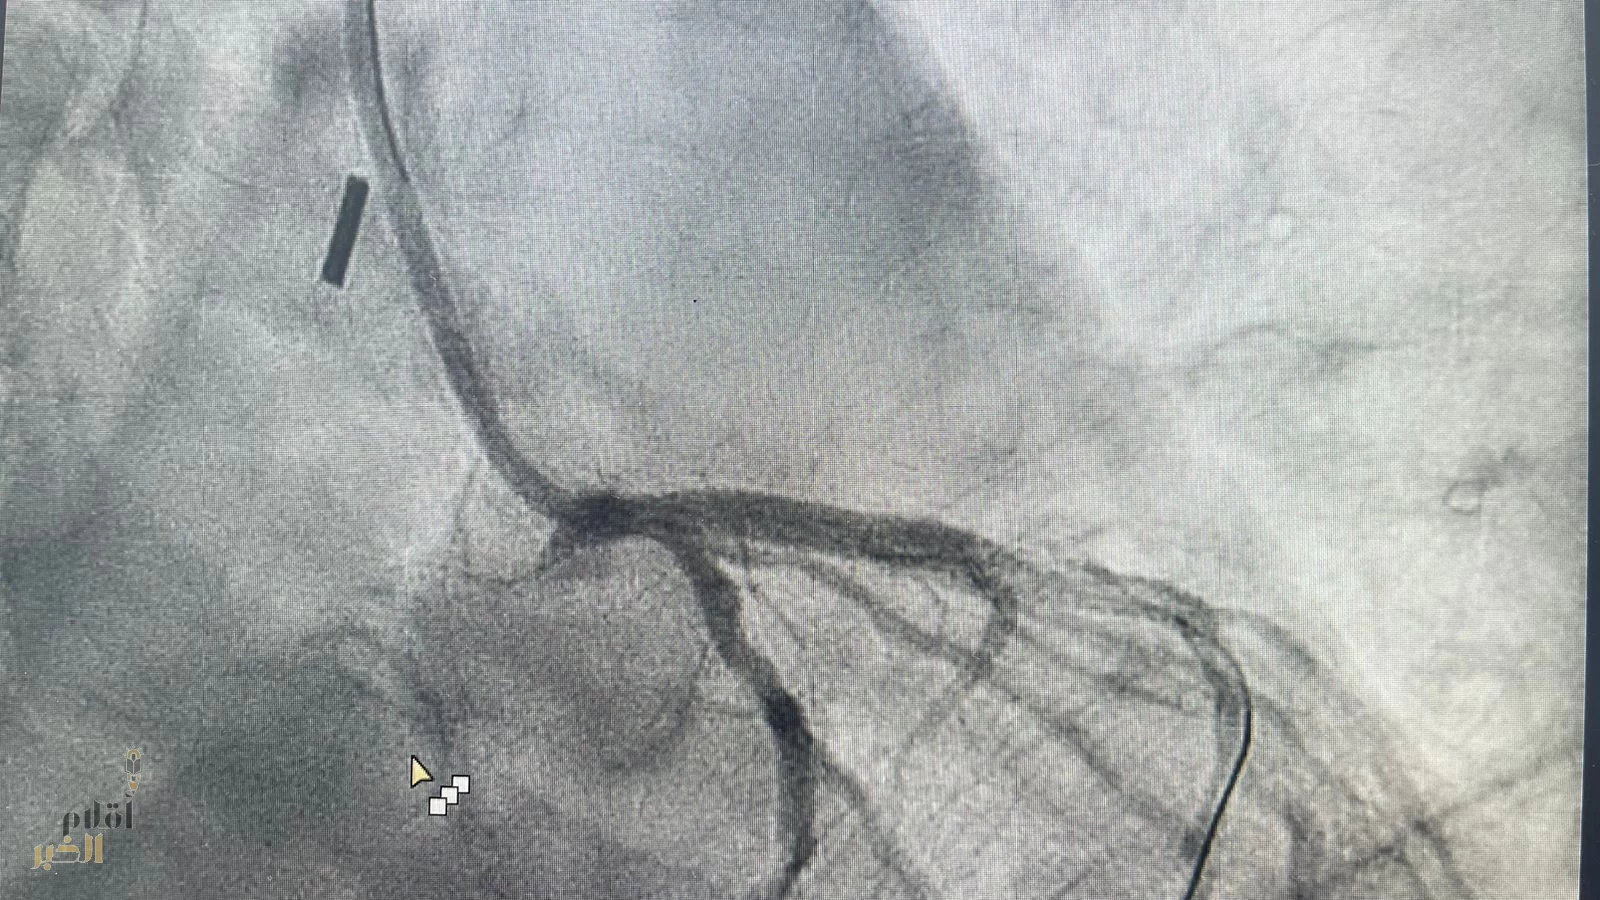

وقال الفريق الطبي المعالج بأنه بعد تفعيل مسار الجلطات القلبية ووصول الفريق الطبي من قسم القسطرة القلبية تم التعامل مع المريض وتبين أن هناك تضيق شديد بنسبة ٩٩ ٪ في الشريان الأيسر الرئيسي كاد أن يودي بحياة المريض ، حيث ان هذا الشريان يغذي ٧٠٪ من عضلة القلب ويحتاج الى تدخل جراحي عاجل لزراعة الشرايين "عملية قلب مفتوح".

وأشار الفريق الطبي بأنه تم خلال القسطرة وضع مضخة داعمة للدورة الدموية في الشريان الأبهري لتحسين كفاءة عضلة القلب ووضع دعامة لفتح الشريان وتحسين تدفق الدم للعضلة واستقرار حالة المريض وتكللت ولله الحمد بالنجاح وتم متابعة حالة المريض وقد خرج في اليوم التالي.